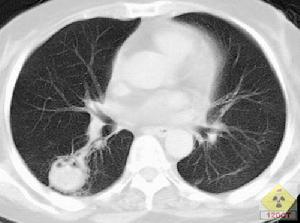

其他輔助檢查:X線表現為雙肺基底部結節影、片狀模糊浸潤陰影,肺門和縱隔淋巴結腫大,偶爾可見胸腔積液。吸入性原發性肺炎,在起病24h內就可見片狀陰影,進一步可出現ARDS或肺水腫樣改變。